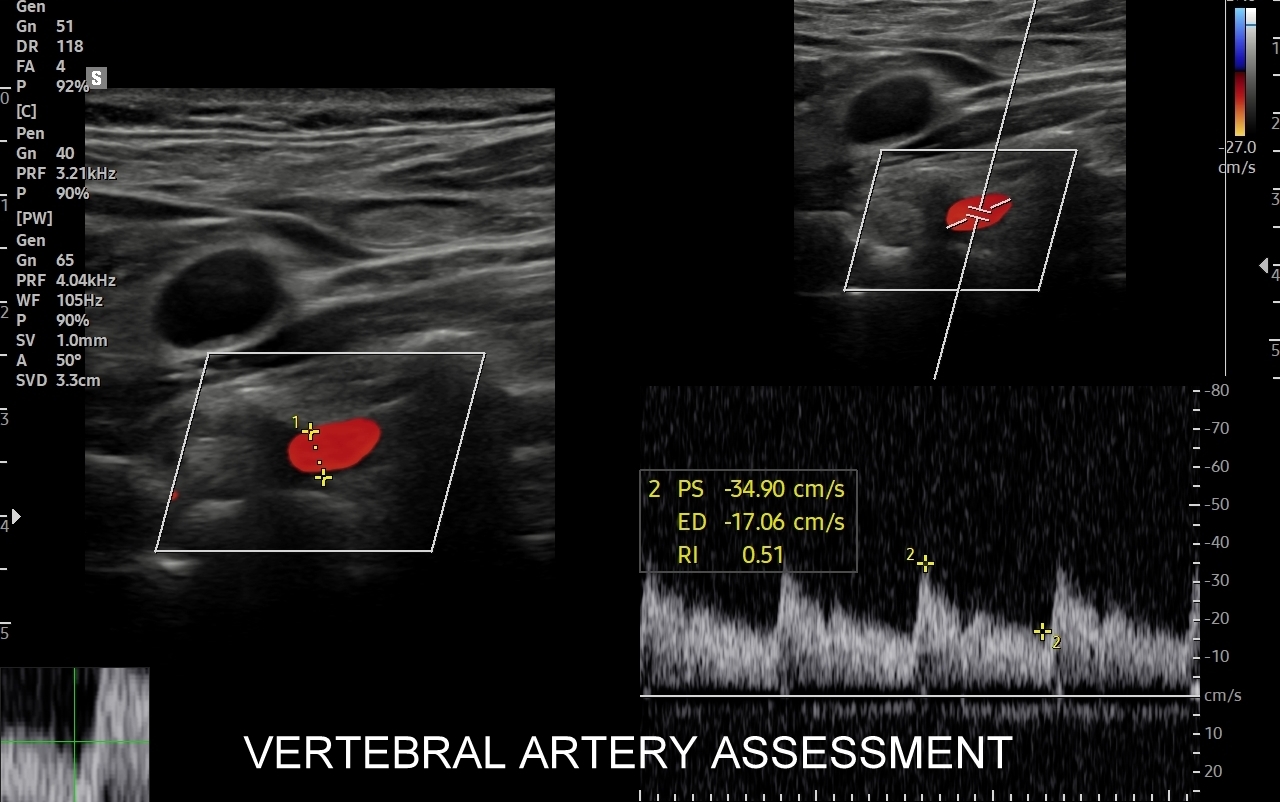

USG tętnic szyjnych i kręgowych

Badanie USG Doppler tętnic szyjnych i kręgowych, określane również jako badanie USG tętnic dogłowowych, to najczęściej wykonywane badanie diagnostyczne w układzie tętniczym. Wynika to z faktu, iż wymienione naczynia doprowadzają krew do jednego z najważniejszych organów człowieka, tj. mózgu, a choroby lokalizujące się w tętnicach dogłowowych mogą być źródłem różnorodnych objawów neurologicznych począwszy od zaburzeń pamięci i widzenia, poprzez bóle i zawroty głowy, aż do zgonu na tle nagłego udaru niedokrwiennego. W trakcie standardowego badania USG tętnic dogłowowych oceniane po obu stronach są tętnice szyjne wspólne, wewnętrzne, zewnętrzne oraz tętnice kręgowe. Badanie niejednokrotnie rozszerza się o specjalistyczną ocenę USG łuku aorty, USG tętnic podobojczykowych, USG tętnic skroniowych, czy o badanie USG Doppler przezczaszkowy.